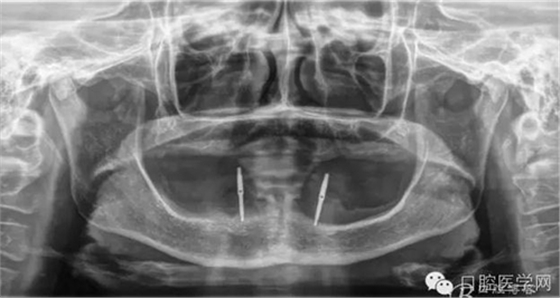

種植體植入后